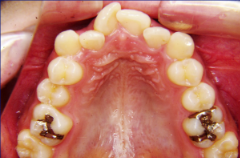

ステップ5.精密検査

口腔内写真,レントゲン

(必要に応じてCT)

印象(歯型)採得

口腔内写真、レントゲン(必要に応じて CT )、印象(歯型)採得